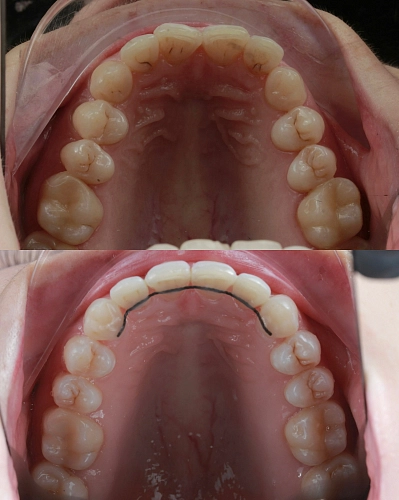

Клинический случай:

Рассмотрим пример ортодонтической коррекции на брекет-системе Damon Q. В данном случае срок лечения составил 1 год и 10 месяцев. За этот период удалось решить несколько важных задач:

• Устранение скученности зубов

• Коррекция наклона верхнего зубного ряда

• Удаление сильно разрушенного зуба на нижней челюсти и закрытие образовавшегося промежутка своими зубами

• Откорректированный прикус и центры зубных рядов

Работа была выполнена врачом-ортодонтом Глуховой Т.А., который тщательно подошел к каждому этапу лечения, чтобы достичь оптимального результата.